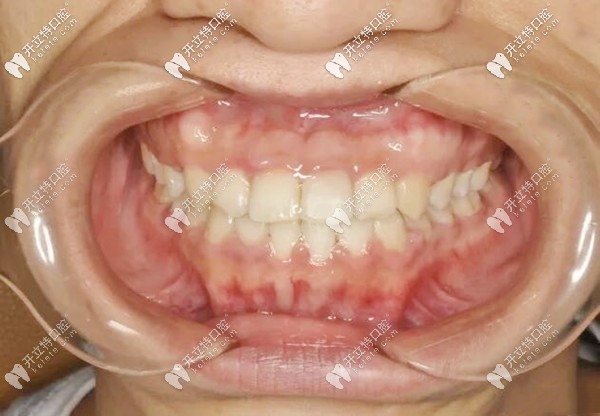

地包天牙齒矯正后的照片▲

矯正前牙齒問(wèn)題:前牙反頜(地包天)+輕微偏頜,影響咬合和臉型;